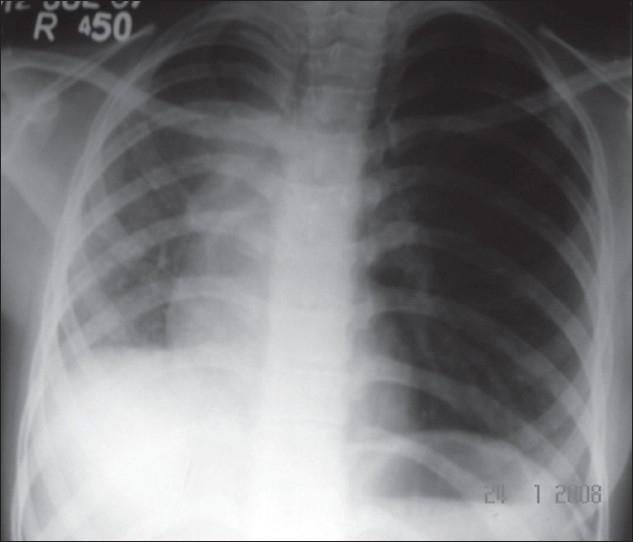

Scimitar syndrome: A rare disease with unusual presentation.

Scimitar syndrome is a rare congenital disorder. It has a varied presentation. In adult life, it usually presents either as recurrent chest infection and/or exertional dyspnea. Pulmonary artery hypertension and hemoptysis both are uncommon features of this syndrome in adult life.